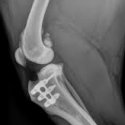

Naast de jaarlijkse gezondheidscontrole en het uitvoeren van routineoperaties zoals castratie en sterilisatie beschikking wij over een goed uitgerust laboratorium waar wij o.a. bloed-en urineonderzoeken uitvoeren, digitale röntgen en een echoapparaat waardoor we snel kunnen handelen als uw dier ziek blijkt te zijn.

Elke vestiging heeft een volledig uitgeruste operatiekamer waar diverse ingrepen worden uitgevoerd. Buiten de steriele ruimtes worden o.a. de gebitsbehandelingen uitgevoerd.